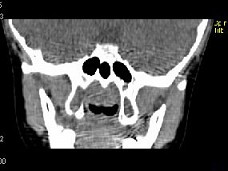

4.女,8岁,头痛,鼻塞半年余,CT如图所示,最可能诊断为 ( )![]() ![]() ![]() ![]() |

| 正确答案:C |